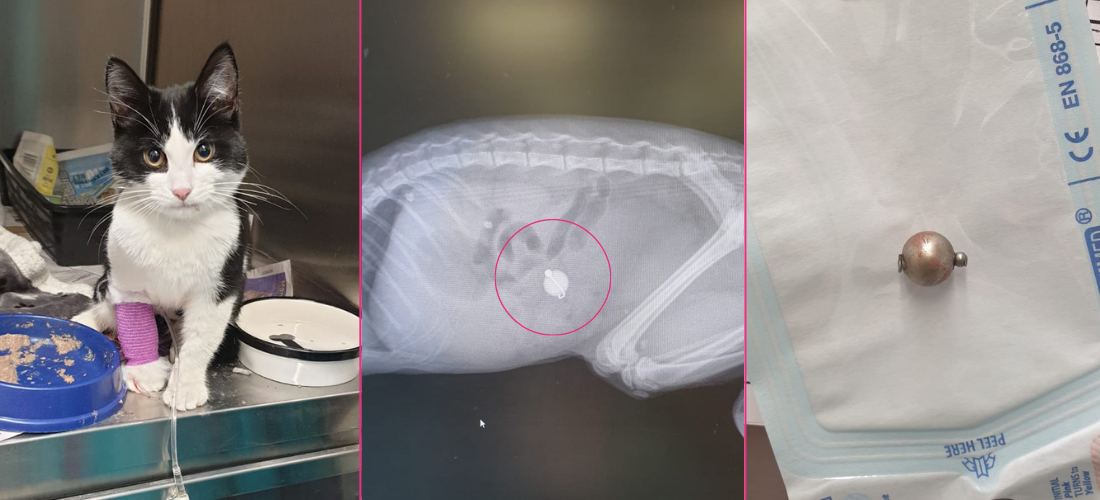

PDSA vet, Laura Hodgkiss, said: “When we examined Louie, we were worried he might have something stuck inside his stomach. An x-ray revealed he had a spherical-shaped object in his intestines, which we needed to remove as soon as possible. On Christmas Day, he underwent emergency surgery, and we discovered the foreign object was a metal bell! Luckily the operation was a success. Afterwards, we kept Louie in overnight for monitoring.”

Simone continued: “We were so shocked to find out Louie had eaten a bell! He must have got his paws on it from our Christmas decorations on the tree. I never even considered this might happen; we certainly won’t be leaving them in paws’ reach in the future.”